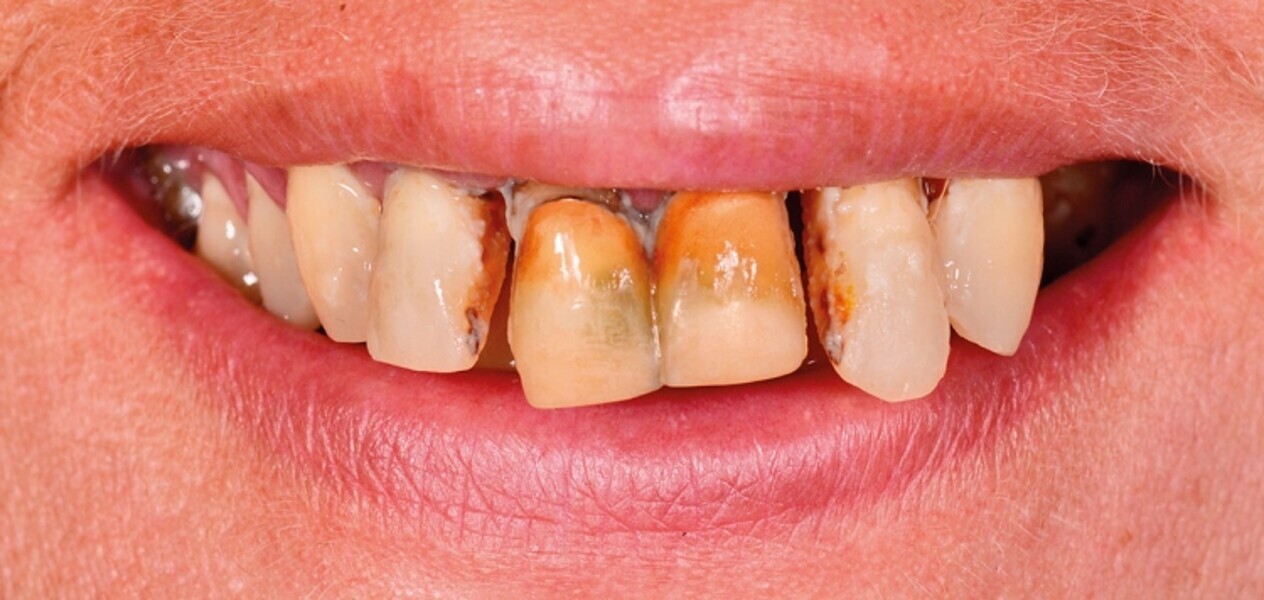

Protocollo SKY fast & fixed